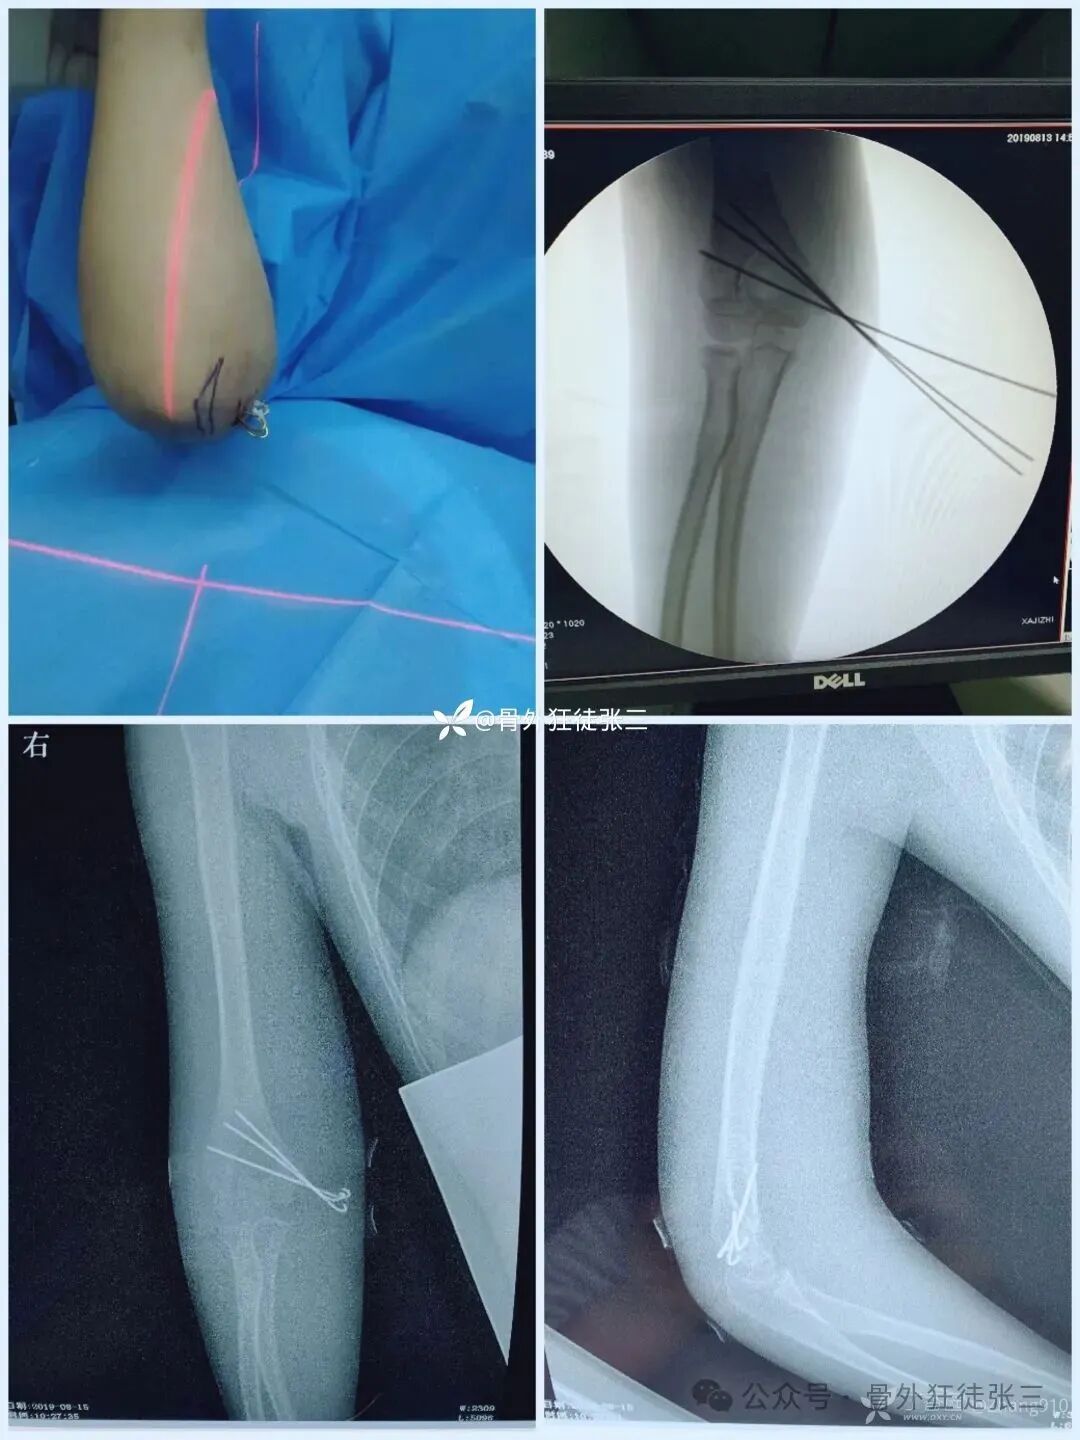

病例4,髁上骨折

(以下髁上骨折,术后处理方案同方案1)

病例6,桡侧三枚针,发散不完美

病例7,桡侧三枚针,发散完美